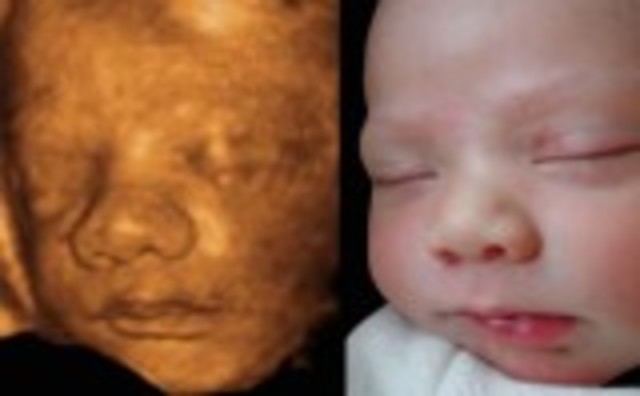

• Week 28

Week 28

Hair is visible through 4D ultrasounds. Milk teeth have started growing under the gums and eyes start to move.